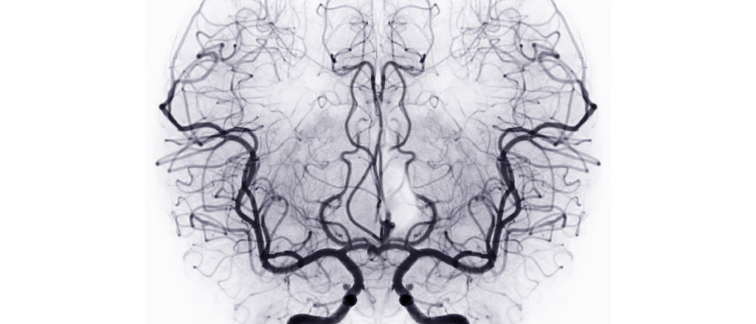

Aneurysmal subarachnoid hemorrhage (aSAH) is a disastrous type of brain hemorrhage associated with high morbidity and mortality. Given the relatively young age of affected patients (with an incidence peak between 50 and 60 years), this condition leads to a substantial loss of productive life years and is associated with the highest average healthcare costs among all stroke subtypes.

A major and feared complication in patients with aSAH is delayed cerebral ischemia (DCI). DCI occurs in approximately 25% of patients and is the leading contributor to poor outcomes after aSAH. However, predicting which patients will develop DCI remains highly challenging. Currently, no clinically available early predictors exist for DCI development. As a result, all aSAH patients are admitted to the hospital for at least two weeks to monitor who will develop DCI. Consequently, approximately 75% of patients who will not develop DCI are also hospitalized for 14 days to monitor their clinical course.

Professor Verbaan and her colleagues aim to address this issue by analyzing biomarker profiles in blood samples from patients with aSAH to improve early prediction of DCI. Earlier identification of patients at low risk of DCI could shorten hospital stays and enable earlier initiation of rehabilitation, potentially improving clinical outcomes and quality of life. In addition, reducing hospital admission by even one week could lower healthcare costs by an estimated €5,000 per patient.

Verbaan and her team propose that blood-based biomarkers may provide a solution. Due to the complicated pathophysiology of DCI, it is expected that reliable prediction of DCI should include not only clinical and radiological variables, but also biological molecular biomarkers. Sophisticated bioinformatics algorithms will be employed to select the most promising and robust markers for test validation. The researchers hypothesize that a selection of a biomarker panel from multiple complementary blood-based biomolecules, including blood plasma proteins, blood platelet RNAs, and the dynamic blood coagulation ROTEM-analyses, which are related to the main underlying pathophysiological processes of DCI, can result in 1) earlier identification of aSAH patients who will not develop DCI, and 2) new insights into its pathophysiology and thereby potential novel treatment targets.